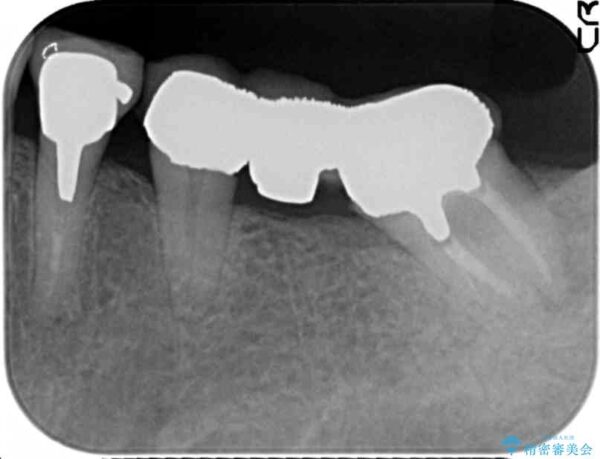

ブリッジ、虫歯を丁寧に除去したのち精密なジルコニアクラウンの作製を行い咬合機能をしっかりと回復します。

ブリッジの支台となる後方臼歯は清掃性が悪く虫歯が大きくなっていたため、抜去を行いインプラントを用いた治療としました。